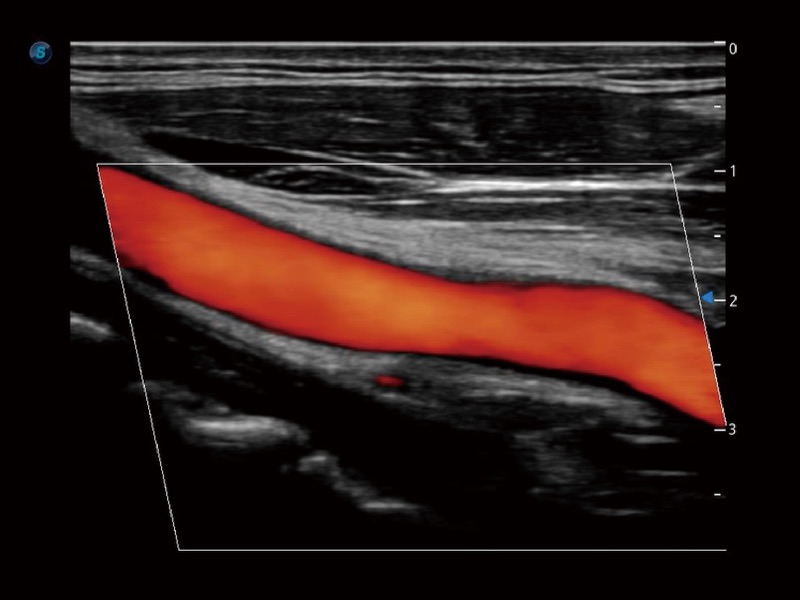

• SR Flow

Como nueva tecnología innovadora, SR Flow mejora la capacidad de detectar señales de flujo de baja velocidad. También mejora la resolución espacial y sortea el sobreflujo para presentar a los usuarios información hemodinámica real.

Arteria carótida